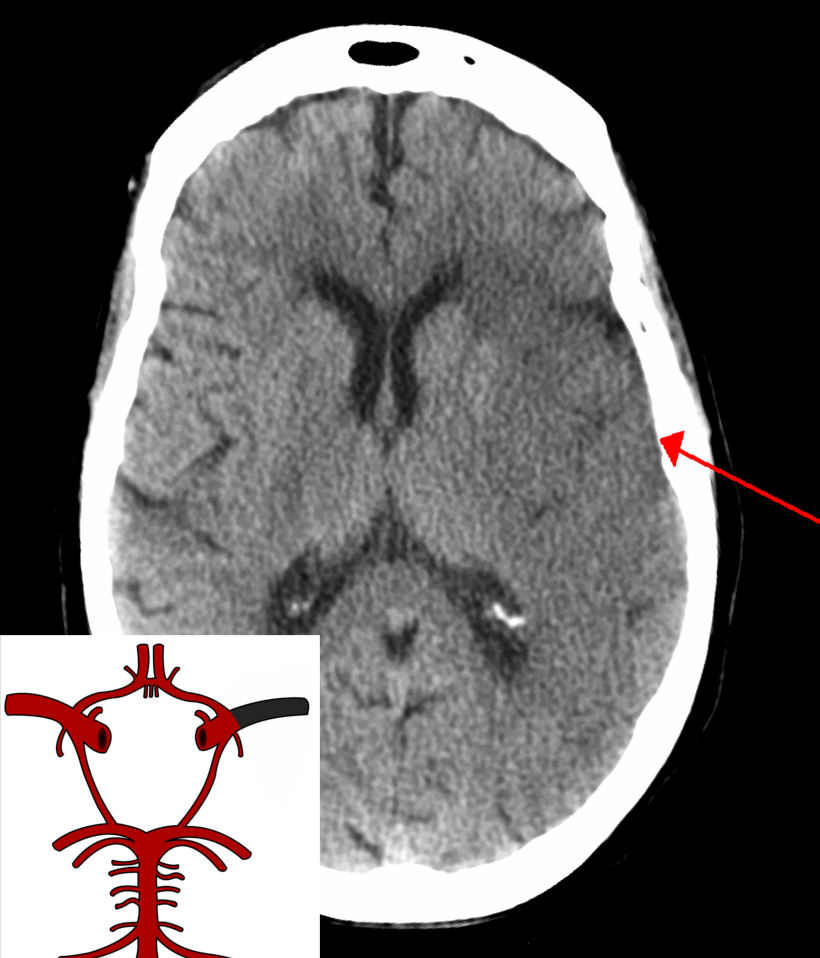

Example 2

Take a look at the following example showing consolidation. Click on the box to reveal the diagnosis.

Diagnosis

Ischaemic Stroke